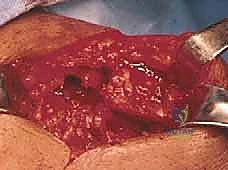

يُجري الجراح شقاً جراحياً دقيقاً (حوالي 5 إلى 7 سم) فوق مفصل الكتف. يتم فصل ألياف العضلة الدالية (Deltoid) بعناية فائقة للوصول إلى الكفة المدورة دون إتلاف العضلات السطحية.

المرحلة الثانية: تجميل الأخرم (Acromioplasty) وإزالة الضغط

قبل إصلاح الوتر، يجب معالجة سبب التمزق. يقوم الدكتور هطيف بإزالة الجراب الملتهب (Bursa) الذي يسبب الألم. ثم يستخدم أدوات دقيقة لإزالة النتوءات العظمية من أسفل عظمة الأخرم، مما يوسع المساحة ويمنع احتكاك الوتر المُصلح لاحقاً.